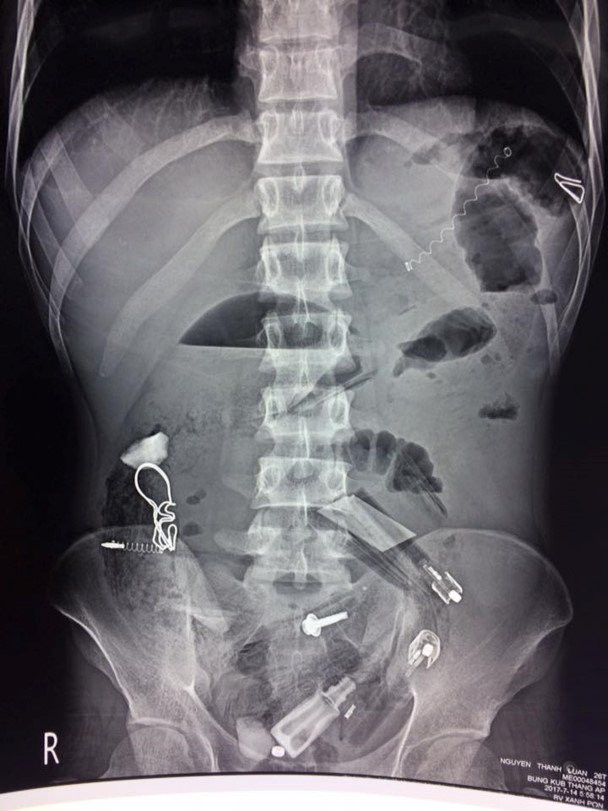

Các bác sĩ chụp Xquang và phát hiện rất nhiều dị vật trong cơ thể bệnh nhân

Kết quả chụp X quang cho thấy, trong dạ dày bệnh nhân có rất nhiều dị vật nên chỉ định phẫu thuật. Trong quá trình thực hiện, các bác sĩ đã lấy ra rất nhiều dị vật như bật lửa, lò xo bút bi, bút bi, thìa nhựa, lá cây, vỏ kẹo, vỏ thuốc, đinh…, tổng cộng hơn 30 dị vật.